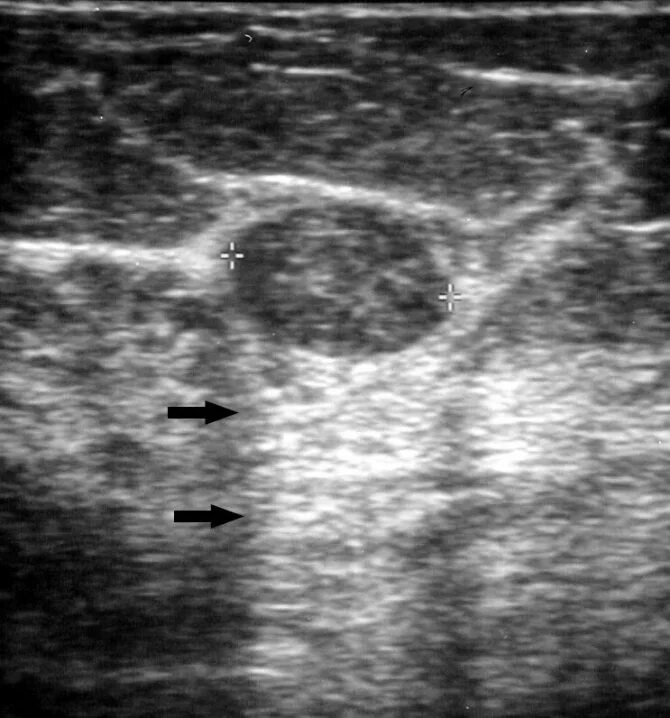

Как выглядит фиброаденома молочной железы